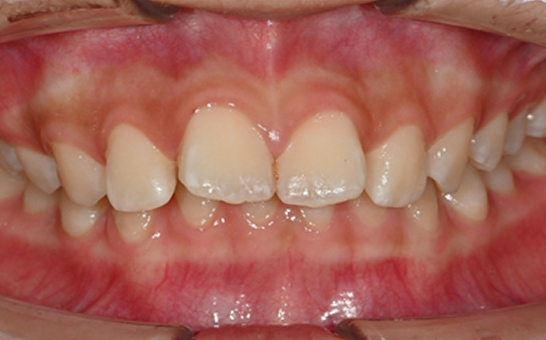

인비절라인 퍼스트(Invisalign First)는 어린이와

성장기 청소년을 위한 투명 교정 장치로, 치아와 턱뼈가

성장하는 과정에 맞춰 설계된 교정 시스템입니다.

해당하는 증상이 있다면 전문의와 상담 후 조기 교정 시

성장기 어린이에게 교합이 틀어지는것을 미리 예방 할 수 있습니다.

※ 바른선택치과의원은 의료법을 준수하며 위 케이스는 실제 내원 환자분의 동의하에 공개된 사진과 동일한 환자분께 같은 조건에서 촬영한 사진을 활용했습니다.

개인에 따라 진료 및 치료 방법이 다르게 적용할 수 있으며, 효과와 부작용이 개인마다 다르게 나타날 수 있는 점을 안내해 드리며, 진료 전 전문의료진과 충분한 상담을 권해드립니다.